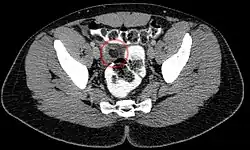

Сальниковые подвески представляют собой небольшие жировые отростки, располагающиеся вдоль поверхности толстой кишки. В результате перекрута или венозного тромбоза в одном из них может развиться воспалительный процесс, проявляющийся резкой болью в одной из областей живота (наиболее часто — в правой или левой подвздошных областях). Иногда возникают тошнота и рвота. Симптомы могут симулировать аппендицит, холецистит или дивертикулит. Температура тела и результаты лабораторных исследований обычно нормальные. Аппендажит обычно диагностируется случайно, при компьютерной томографии, проводимой для исключения более серьёзной патологии. Чаще всего воспалительный процесс локализуется в области слепой или сигмовидной кишок.